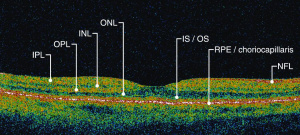

Optical coherence tomography (OCT) is a non-invasive imaging technique which uses reflected light to create high resolution, two or three dimensional representation of retinal architecture. Measurement of the various retinal layers allows for objective, quantitative assessment of structural damage in the visual pathway.[9] OCT has therefore emerged as a non-invasive and relatively inexpensive technique for capturing loss of central nervous system axons and neurons. Because of these advantages, OCT is now being explored as a potential tool to identify retinal changes in patients early in the course of NDDs, and to allow quantifiable, objective monitoring of axonal and neuronal loss with disease progression.

OCT can identify changes in thickness within specific quadrants of the retina. Abnormalities in particular quadrants or combinations of quadrants may indicate a certain pathology and aid in distinguishing similar diseases or disease progressions.